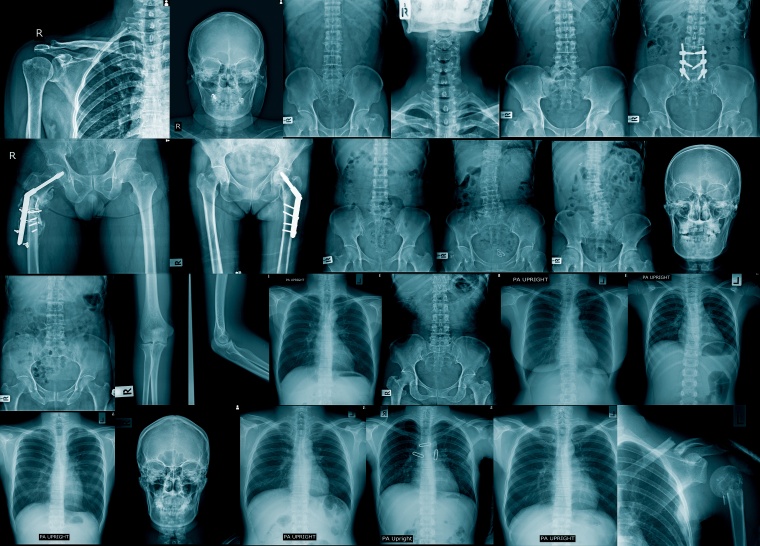

Heute Alltag, seinerzeit eine medizintechnische Revolution: die Entdeckung der Röntgenstrahlen durch Wilhelm Conrad Röntgen vor 125 Jahren in Würzburg. Seine Entdeckung am 8. November 1895 läutete eine neue Ära in der Medizin ein, die bis dahin unbekannte Einblicke in den menschlichen Körper ermöglichte. Bereits wenig später konzentrierten sich die Unternehmen Siemens & Halske und Reiniger, Gebbert & Schall (RGS) – die beiden Vorgängerfirmen von Siemens Healthineers – auf die industrielle Herstellung von Röntgenröhren und -apparaten und prägten damit die weitere Entwicklung der Technologie entscheidend mit. Heute ist die Röntgentechnik die Grundlage für viele bildgebende medizinische Geräte und damit aus dem Alltag nicht mehr wegzudenken. Siemens Healthineers nimmt das Jubiläum zum Anlass und würdigt Wilhelm Conrad Röntgens bahnbrechende Entdeckung, die das Leben der Menschen nachhaltig zum Positiven verändert hat, mit einem umfassenden Themenjahr.

Der in Würzburg lehrende Physik-Professor entdeckte die Strahlen – er selbst verwendete den Begriff X-Strahlen – beiläufig beim Experimentieren mit Gasentladungen, die in einer Glasröhre mit zwei eingeschmolzenen Elektroden erzeugt werden. Das dabei entstehende Leuchten lässt sich mit Hilfe eines Leuchtschirms beobachten. Als er solch eine Glasröhre lichtdicht verpackte und den Raum abdunkelte, bemerkte er, dass ein Leuchtschirm neben der lichtdicht verpackten Röhre in der Dunkelheit zu leuchten begann. Er vergrößerte den Abstand, doch die Strahlung wirkte unverändert, lediglich Platin und Blei konnten diese aufhalten. Schließlich hielt er seine Hand in die Strahlen und sah auf dem Leuchtschirm die Schatten seiner Handknochen. Als Beweis hielt er seine Entdeckung mit Hilfe der Fotographie fest. Dies war die Geburtsstunde der Röntgentechnik. Bereits drei Tage nach Bekanntwerden der Entdeckung der X-Strahlen machten sich Reiniger, Gebbert & Schall an die Entwicklung der ersten Röntgenröhre, die später von Röntgen gekauft wurde. Die Röntgentechnik kommt im Portfolio von Siemens Healthineers auch heute weiterhin breit zum Einsatz: Von der Computertomographie über Mammographie bis hin zur klassischen Radiographie. Darüber hinaus bietet Siemens Healthineers mit seinen Angiographie-Systemen und mobilen C-Bögen innovative, bildgestützte Therapiekonzepte und minimalinvasive Verfahren.